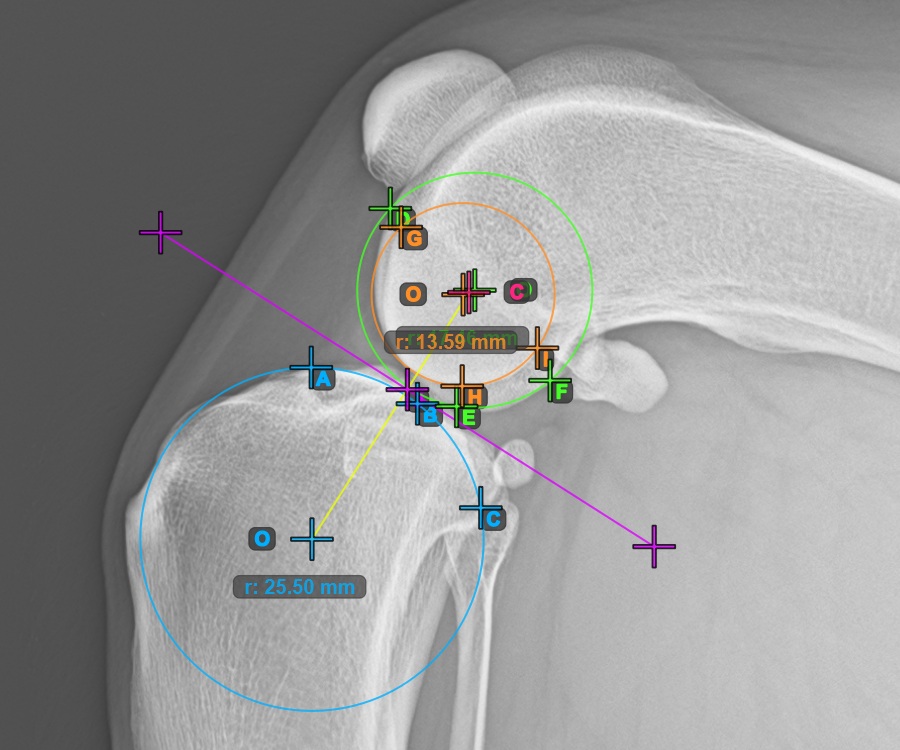

Kezdje el a mérést a három pont megjelölésével a Condylus Medialis Tibialis-on.

Jelölje meg a három pontot a tibia fő condylusán (Medialis Tibialis). A sorrendtől függetlenül ügyeljen arra, hogy megjelölje a legfelső pontot, a legalacsonyabb pontot és a Medialis Tibialis középpontját. A három pont alapján a rendszer automatikusan létrehoz egy kört.

A lenti kép a Condylus Medialis Tibialis-on elhelyezett három pont tipikus elhelyezkedését ábrázolja.